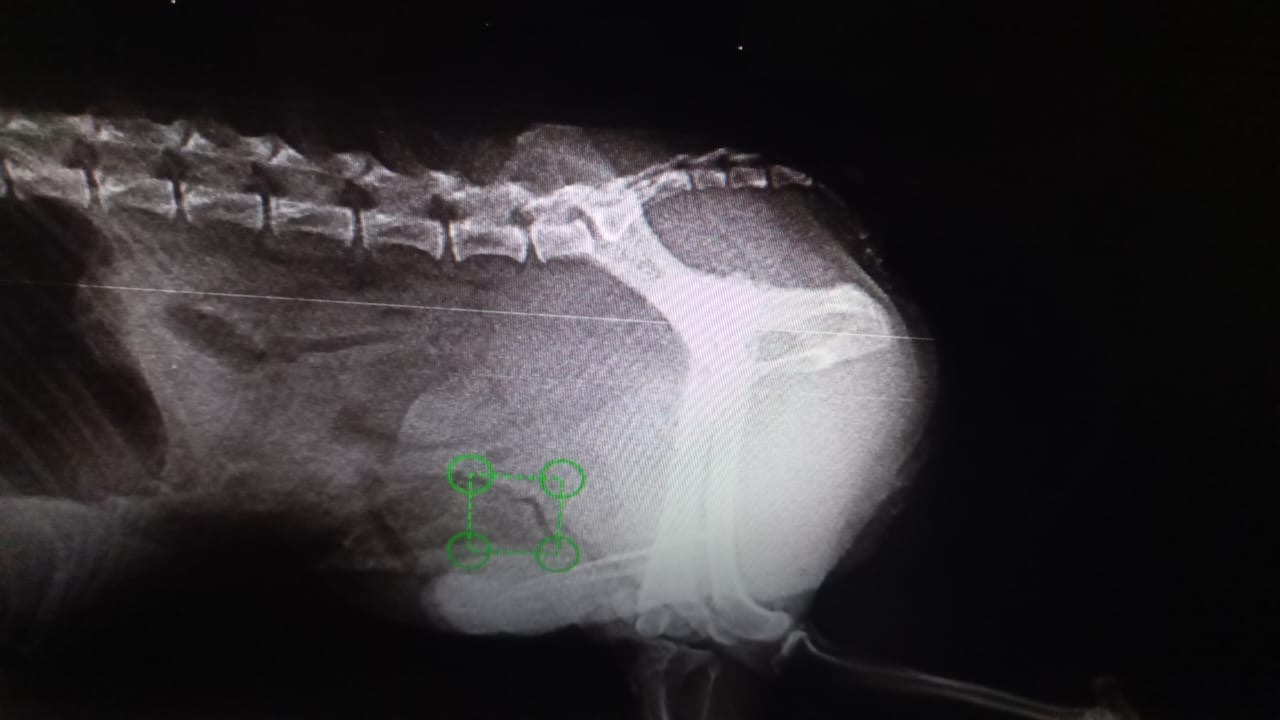

Il est borgne à la suite d’une blessure à l’œil droit non soigné. Il a un souffle au cœur qui sera mieux détaillé à son arrivée en France et son traitement sera adapté. Il a malheureusement été attaqué par un gros chien sans laisse et a été gravement blessé : il a subit 2 chirurgies pour soigner la luxation de la hanche et la hernie abdominale.